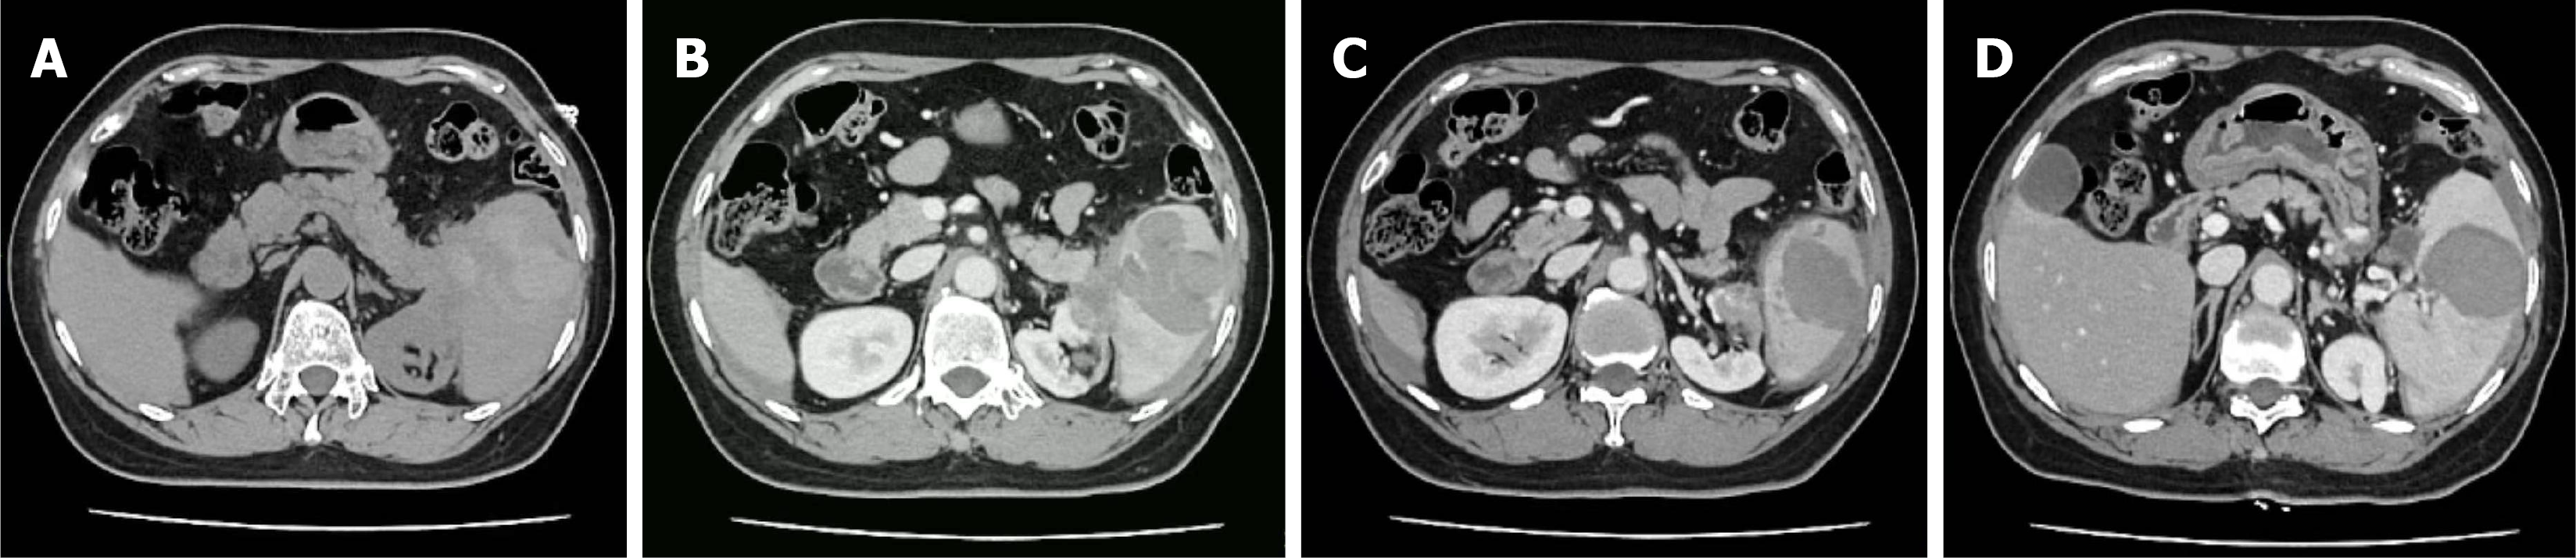

Figure 1 Emergency abdominal computed tomography scan revealed splenic rupture with perisplenic and intraperitoneal hemorrhage.

A: Extensive perisplenic hemorrhage with obscuration of the normal anatomic interface between the pancreatic tail, spleen, and kidney; B and C: Disruption of the renal parenchyma observed on different computed tomography planes; D: A hypodense fluid-filled area within the spleen.